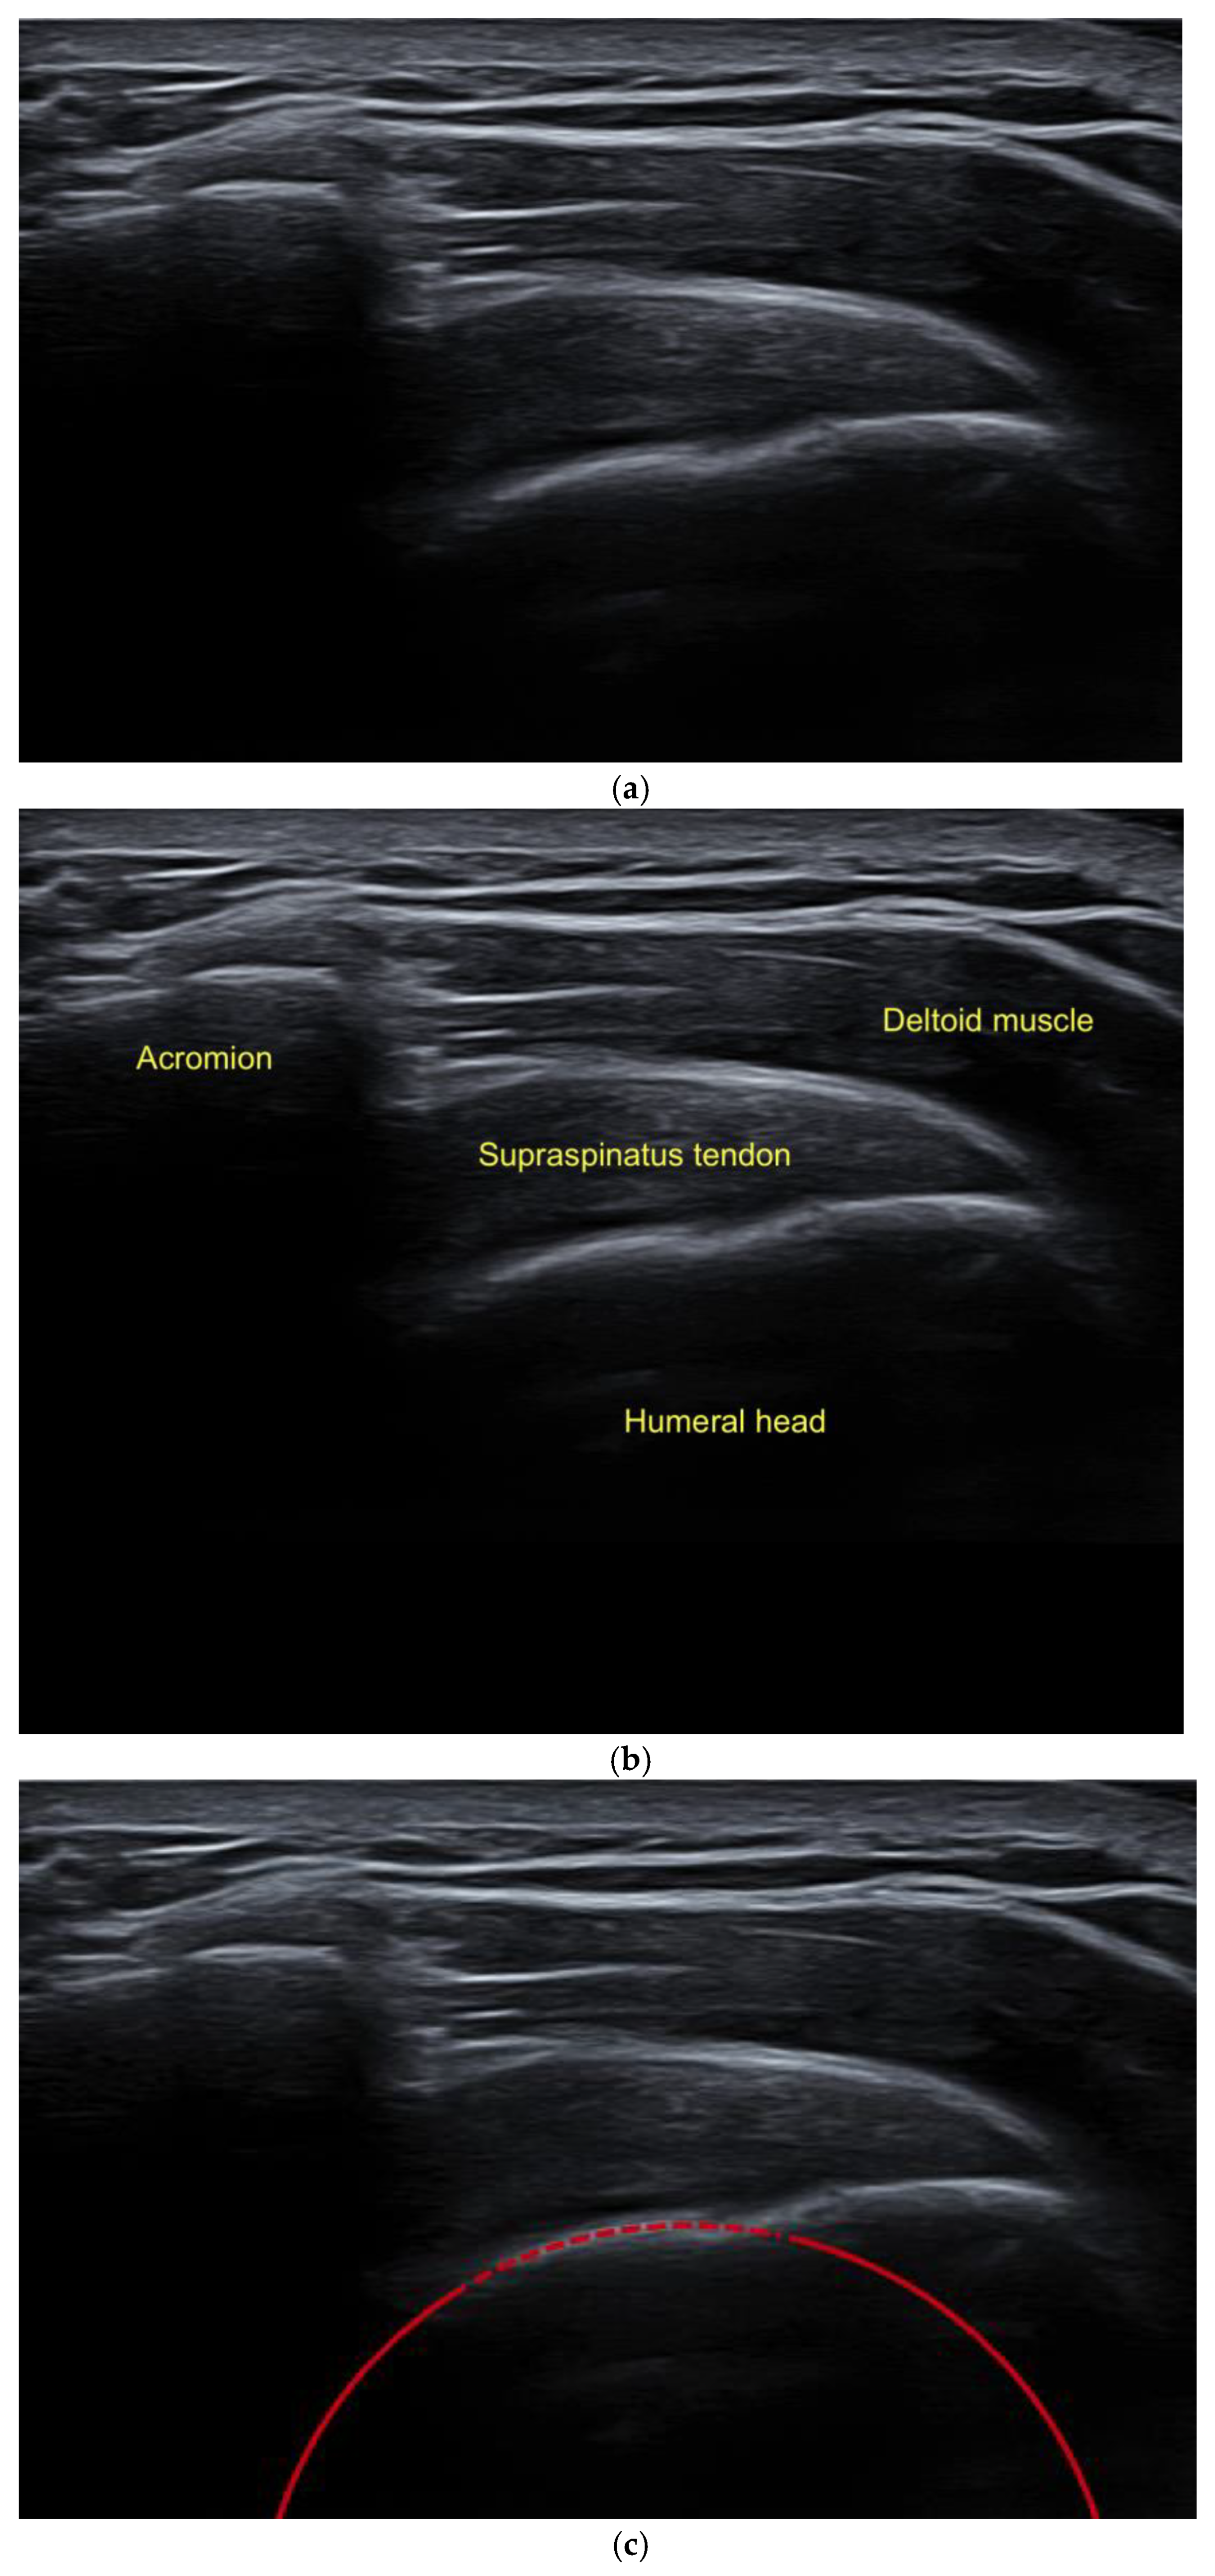

- The examination of a patient was performed in a sitting position, ensuring that the arm being examined was not placed in an abducted posture, and the circular structure of the humeral head was included in the imaging (Figure 2).

- To ensure the accurate determination of the modified critical shoulder angle (mCSA), the lateral aspect of the acromion and the sphericity of the humeral head were visualized in the superior longitudinal section, and all relevant anatomical structures needed to be identified (Figure 3a,b).

- Subsequently, utilizing an image viewing, editing, and measuring program (Centricity, Universal Viewer Zero Footprint Client, Version: 6.0 SP11.2.3), the sonographically visualized circular section of the humeral head was expanded to a complete circle. This method facilitated the precise identification of the central point of the humeral head (Figure 3c).